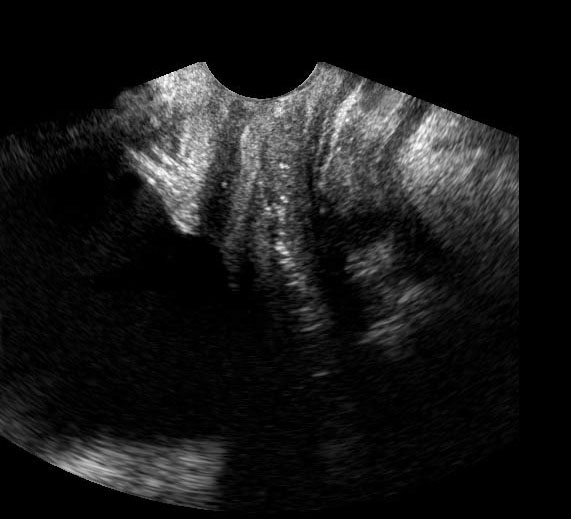

TVUS cho thấy dày thành trực tràng do phù nề với hình thái trực tràng còn lại bình thường, và một khối giảm âm không điển hình (*) ở phía sau bên phải, được bao quanh bởi mô mỡ tăng âm không thể nén ép.

Khối cảm giác rất cứng khi thăm khám. Chẩn đoán gợi ý là một thể DIE không điển hình.

Cuối cùng, sinh thiết qua nội soi đại tràng dưới hướng dẫn siêu âm nội soi (EUS) sâu cho thấy nhiễm trùng xơ hóa mức độ thấp, không có đặc điểm của lạc nội mạc tử cung hay ác tính. Chẩn đoán actinomycosis được đặt ra. Sau sáu tháng điều trị penicillin tĩnh mạch (qua port-a-cath), chỉ còn lại các bất thường tồn dư tối thiểu. Bệnh nhân hết đau. Mười lăm năm trước, bệnh nhân đã được tháo dụng cụ tử cung (IUD). CRP thấp phù hợp với nhiễm trùng mạn tính mức độ thấp kéo dài. Không có bằng chứng vi khuẩn học.